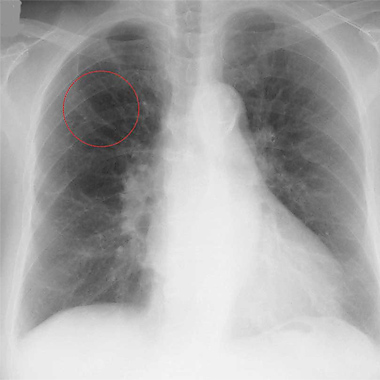

胸部レントゲンと胸部CTの違い

下の画像にあるように左が〈胸部レントゲン〉で右が〈胸部CT〉です。

左の〈胸部レントゲン〉の丸印のところが、右の〈胸部CT〉の矢印のところになります。このように、早期のがんは淡く小さな影で胸部レントゲンでは発見しにくいものです。

したがって、胸部の検診にはCTをお勧めしています。

胸部レントゲン